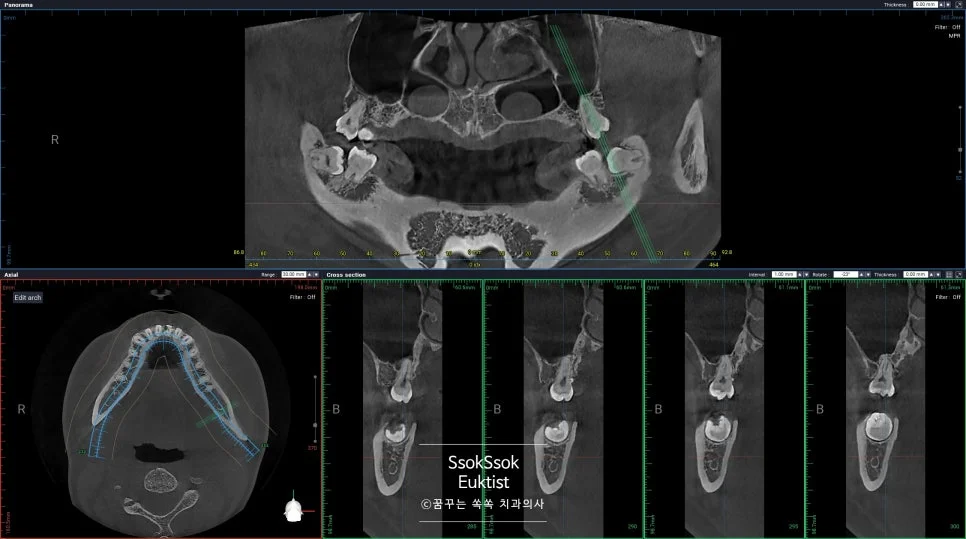

상악동 거상술 임플란트, 발치 후 바로 식립하면 치료 기간을 얼마나 줄일 수 있을까?

케이스1 좌측 상악 결손 파노라마 진단

좋은 진료를 정직하게 | 선한 영향력으로 더 나은 가치를 상악동 거상술 임플란트, 발치 후 바로 식립하면 치료 기간을 얼마나 줄일 수 있을까? 수면 임플란트 상악동 거상술 | 치과의사 박상억입니다 🙂 안녕하세요^^ 치과 임플란트를 고민하고 계신다면, “수술이 너무나도 두렵다” “치료 기간이 너무 오래 걸려 걱정된다” 위와 같은 고민을 하고 계시나요? 많은 분이 임플란트 치료를 미루는 가장 … 더 읽기